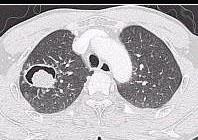

问题 女性,32岁。1个月前诊断为系统性红斑狼疮,经激素治疗症状稍好转。近3天发热、咳嗽、咳少许粘痰。体检:肺呼吸音粗,无啰音。胸部CT示右下肺邻近胸膜处结节影。结节影呈晕轮征(ha1osign)(如图),最可能的诊断是 ( )

选项 A.血源性肺脓肿 B.金黄色葡萄球菌肺炎 C.肺曲菌球 D.原发性支气管肺癌 E.Wegener肉芽肿

答案 C